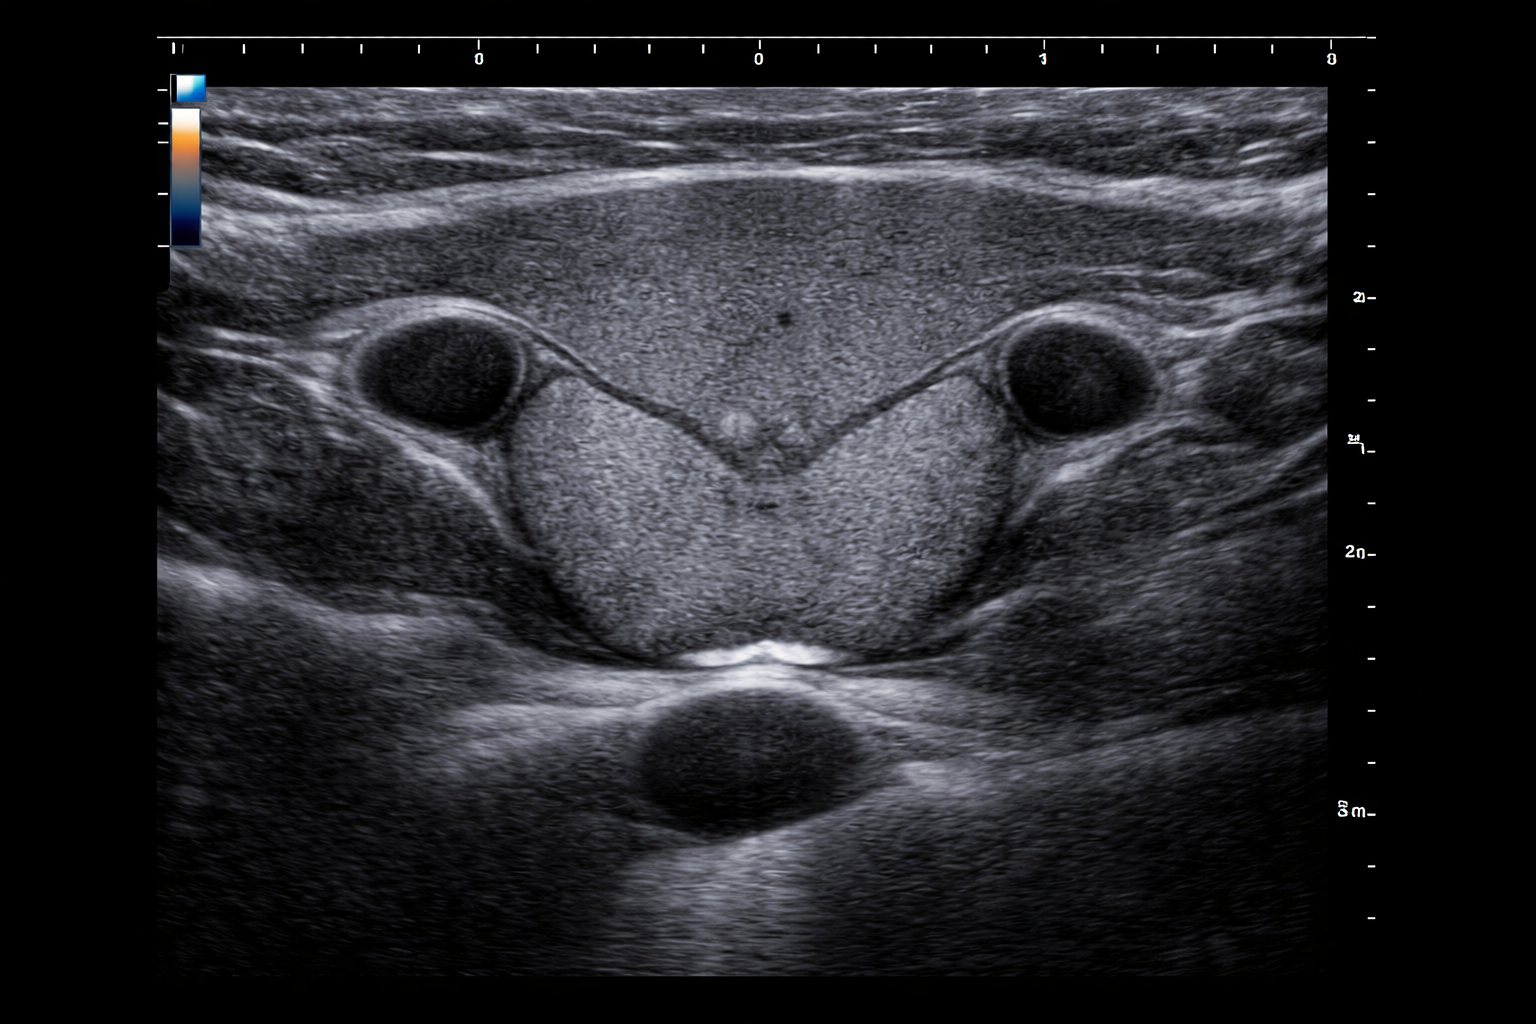

Ultrasound

ID: 9ea1dd88-44e3-43c6-b760-7a0d237af5fa...9ea1dd88-44e3-43c6-b760-7a0d237af5fa

25 yoshli Erkak

22.04.2026 17:20

Yuqori

Tashxis

Malignant (Xavfli)

Saraton xavfi aniqlandi - Zudlik bilan onkolog va endokrinolog bilan bog'laning!

Ishonch

100,0%

TSH

2,5

Tugun

1,5 sm